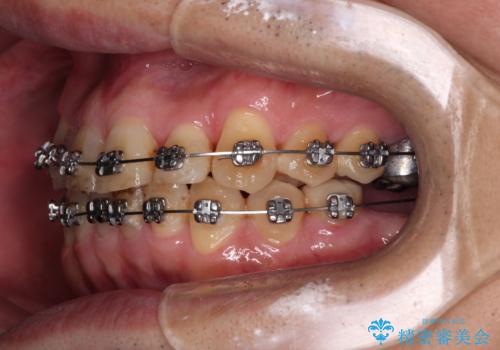

ここまでの治療を提案したところで、折角なのでしっかり治療を行いたいとのことで、前歯のデコボコやクロスバイトを改善するための矯正治療を行うこととしました。

まずは奥歯の痛みを改善し、その後矯正治療を行い、最後にオールセラミックブリッジによる補綴治療を行うこととしました。